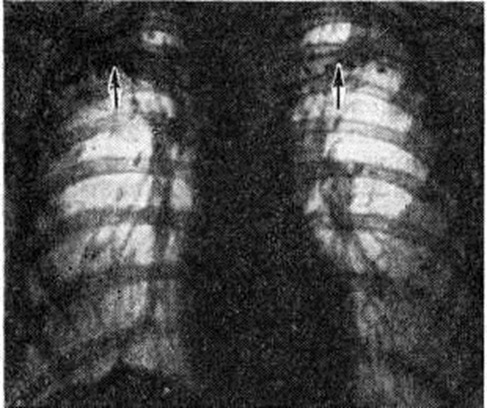

Рис. 5.

Рентгенограмма грудной клетки при милиарном туберкулёзе (прямая проекция): видны множественные тени во всех отделах лёгких, образованные мелкими очагами и инфильтративными интерстициальными изменениями; сосудистый лёгочный рисунок не определяется.